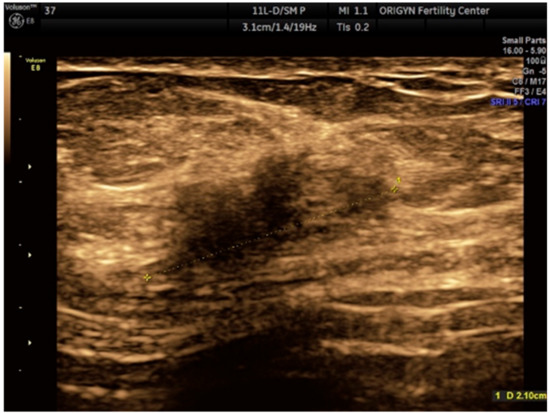

2.1. Case 1